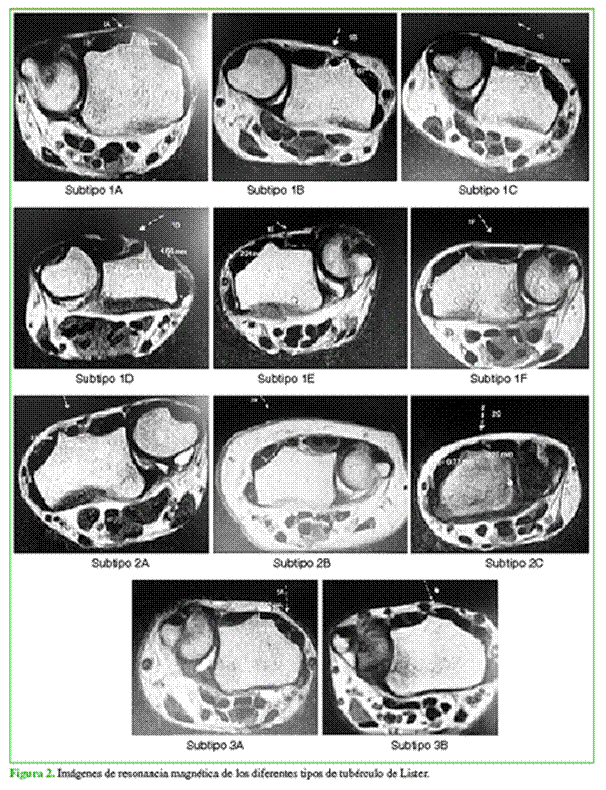

Se evaluaron 500 RM de muñeca (378 derechas y 122 izquierdas) que cumplieron los criterios de inclusión en 328 mujeres y 172 hombres, con un promedio de edad de 42 años (rango 18-87). Sobre la base de los hallazgos, realizamos una subclasificación de los tipos de TL, desprendida de la clasificación de Chan y Chong, y obtuvimos 11 subtipos diferentes.

Tipo 1: Pico radial mayor que el pico cubital

1A: El pico radial es redondeado y es mayor que el cubital, que también termina en un pico redondeado.

1B: El pico radial es redondeado y mayor que el cubital, que en este caso, es mucho menor que el pico cubital tipo 1A y termina con una forma más alargada.

1C: El pico radial es alto y termina redondeado o en punta, pero no es seguido del pico cubital, sino que presenta un largo valle hasta finalizar en un pico pequeño cubital.

1D: El pico radial es mayor que el cubital, pero ambos picos terminan en punta.

1E: El pico radial es redondeado y no presenta un pico cubital, en donde el valle engloba al tercero y cuarto compartimento.

1F: El pico radial es en punta y no presenta pico cubital, en donde su valle engloba al tercero y cuarto compartimento.

2A: El pico radial y el cubital tienen la misma altura >1 mm.

2B: El pico radial y el cubital tienen la misma altura <1 mm y >0,5 mm.

2C: El pico radial y el cubital tienen la misma altura, pero <0,5 mm.

3A: El pico radial es menor que el cubital.

3B: No hay pico radial con un pico cubital prominente.

En la Figura 1, se muestra un esquema de los tipos de TL. En la Figura 2, se presentan imágenes de RM de los diferentes tipos de TL.